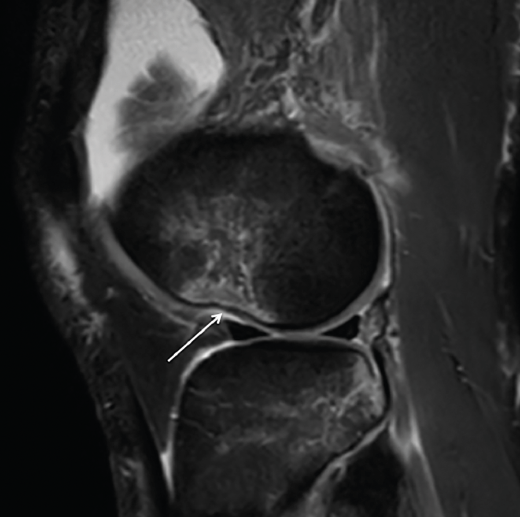

Se ha demostrado la correlación entre los hallazgos en ecografía y RM con alto grado de pivot shift en lesiones de LAL(36,40). Mediante esta exploración pueden detectarse tanto la lesión propiamente dicha del LAL, como la fractura de Segond y otros signos indirectos como la impactación del cóndilo femoral lateral (Figura 3).

Figura 3. Imagen sagital de resonancia magnética del cóndilo femoral externo en la que puede apreciarse el signo de impactación (nocht sign, flecha blanca). Puede interpretarse como signo indirecto de afectación del ligamento anterolateral .

- Signo de la muesca o notch sign(51,59): consiste en una hendidura en el cóndilo femoral lateral causada por el movimiento de rotación del pivot shift, en el que la región posterior de la meseta externa impacta sobre el cóndilo y deja una impronta que, cuando es mayor de 2 mm (no confundir con el sulcus terminal del cóndilo, que rara vez supera 1,5 mm), es considerada patognomónica de lesión del LCA(60).